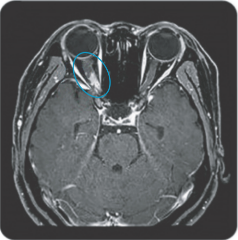

Area postrema syndrome is a core clinical characteristic of NMOSD that can appear both at disease onset and throughout the clinical course7

- The spectrum of NMOSD symptoms is broad and includes nausea, vomiting, and intractable hiccups7,8

- 4 out of 10 NMOSD attacks of the area postrema include all 3 symptoms7

- Due to symptom severity, ~80% of patients with NMOSD-related area postrema syndrome are hospitalized7